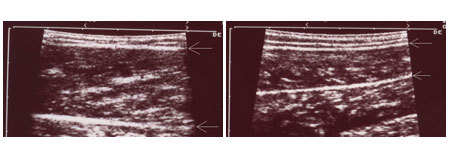

上圖例小姐在做完小腿肌肉手術及小腿抽脂手術後五個月,小腿圍由36.5公分縮減為32.5公分。 這位小姐手術後一年回診,小腿仍保持纖細腿形,超音波檢查內腓的肌肉厚度由術前的21mm減為13mm,肌肉仍然維持功能。